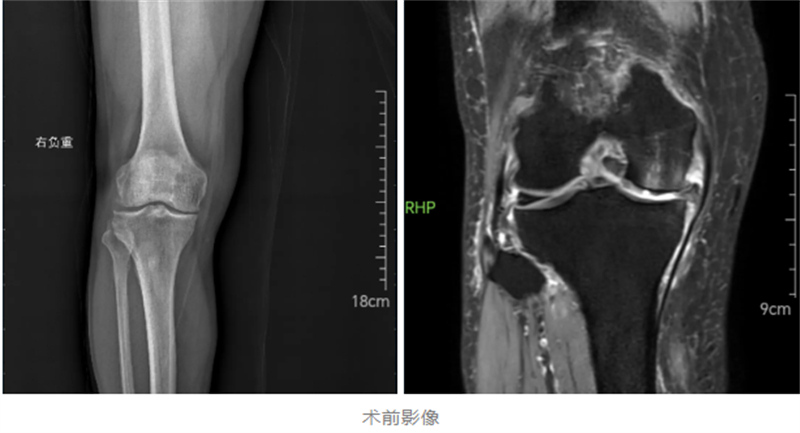

經過詳細檢查,關節骨病科副主任韋健博士診斷楊先生為重度骨關節炎。鑒于患者疼痛集中于膝關節前內側,建議采用損傷小、恢復快的膝關節單髁置換術?!皢西林脫Q就像給磨損的鞋底更換前掌,通過替換病變軟骨面,更多保留正常關節組織。” 韋健博士解釋道。